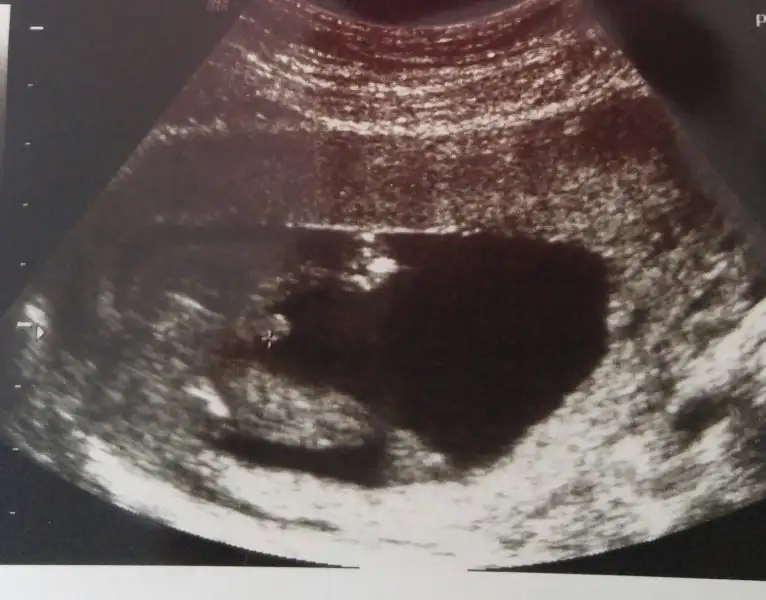

Benimde kizimda senin kiz gibiydi oglumdada simdiki ultrasyon resmin gibiydi. Sanirim bebosin oglan canim :)Eki Görüntüle 1895776 bu kızım 7 yıl önceki ultrason görüntüsü. Eki Görüntüle 1895777 buda şimdi ki

Senin oglum keseye göre tutmus buda kiz bence cünkü teori sende tutuyo :)Karından usg.ilk foto 6+3 ikinci foto 7 haftalık.

6 ile 8 hafta arası usg görüntü varsa gönder.arkadaşlar yorum yaparlar.hayırlısı olsun